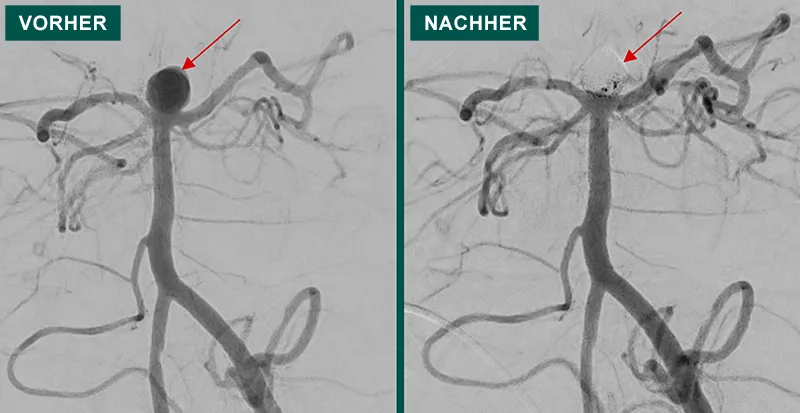

Coiling Das Coiling ist ein minimalinvasives Verfahren zur Behandlung von zerebralen Aneurysmen – krankhaften Erweiterungen oder Ausbuchtungen in den Hirngefäßen. Diese Aneurysmen können lebensbedrohlich sein, da sie reißen und zu schweren Hirnblutungen führen können. Ziel des Coiling ist es, das Aneurysma von innen heraus sicher zu verschließen, um eine Ruptur zu verhindern.

Diese Intervention wird unter stationären Bedingungen in Vollnarkose vorgenommen. Über einen kleinen Zugang in der Leistengegend wird ein dünner, flexibler Katheter in die Arterie eingeführt und unter Röntgenkontrolle bis zum betroffenen Hirngefäß vorgeschoben. Dort wird das Aneurysma lokalisiert, und anschließend werden über den Katheter feine Platinspiralen, sogenannte „Coils“, in die Aneurysmahöhle eingebracht. Diese Spiralen fördern die Blutgerinnung innerhalb des Aneurysmas, wodurch sich ein stabiler Verschluss bildet. So wird kein erhöhter Druck mehr auf die krankhafte Aussackung ausgeübt.

Im Vergleich zu einer offenen Operation am Gehirn (Clipping) ist das Coiling deutlich schonender und mit einem geringeren Risiko verbunden. Es erfordert keinen großen chirurgischen Eingriff am Schädel und führt meist zu einer schnelleren Genesung. Das Verfahren ist insbesondere durch moderne Entwicklungen von Materialien praktisch für alle Aneurysmen im Gehirn und bei allen Patienten, die eine DSA erhalten dürfen, geeignet. Nach dem Eingriff sind regelmäßige Kontrolluntersuchungen mittels bildgebender Verfahren wie der Magnetresonanztomographie (MRT) oder der digitalen Subtraktionsangiographie (DSA) wichtig. Diese dienen dazu, den Verschluss des Aneurysmas zu überprüfen und frühzeitig mögliche Nachbehandlungen zu planen. Wie bei allen medizinischen Eingriffen können auch beim Coiling Komplikationen auftreten, etwa Blutungen, Gefäßverletzungen oder eine unvollständige Verschließung des Aneurysmas. Dank moderner Technik und großer Erfahrung der behandelnden Ärzte sind diese Risiken jedoch gering.

Das Coiling ist heute eine etablierte, sichere und effektive Therapieoption zur Behandlung von Hirnaneurysmen. Es trägt entscheidend dazu bei, lebensbedrohliche Hirnblutungen zu verhindern und die Lebensqualität der Patienten zu erhalten.